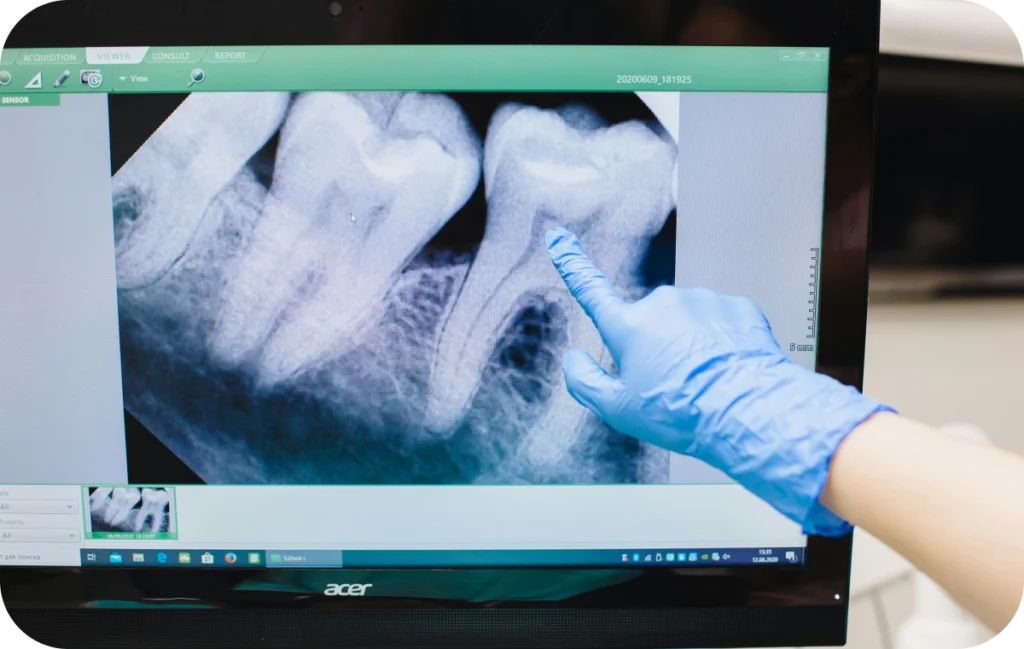

Le recours à l’endodontie est souvent motivé par des symptômes précis. Une douleur persistante, une sensibilité marquée à la chaleur ou au froid, ou encore une douleur à la mastication sont des signaux qui peuvent indiquer une atteinte de la pulpe. Parfois, l’infection peut évoluer de façon silencieuse et être découverte lors d’un examen radiographique de contrôle.

L’endodontie est une discipline de la dentisterie qui s’intéresse à la partie interne de la dent, appelée pulpe dentaire. Cette zone, protégée par l’émail et la dentine, contient les nerfs et les vaisseaux sanguins qui assurent la vitalité de la dent. Lorsqu’elle est infectée ou gravement atteinte par une carie ou un traumatisme, il est nécessaire d’intervenir pour soulager la douleur et préserver la dent.